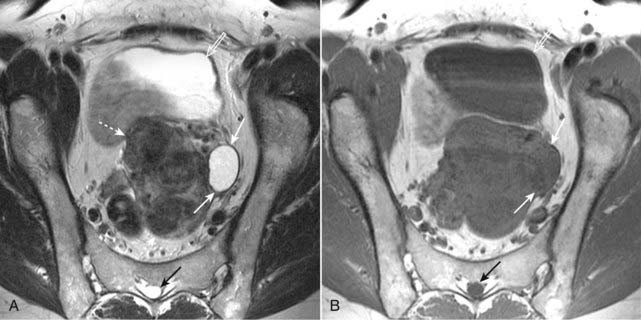

Figure 20-4 Simple left ovarian cyst.

A, Axial T2-weighted image demonstrates an ovoid, homogeneously bright lesion in the left ovary (solid white arrows) adjacent to a fibroid uterus (dotted white arrows). Note that urine in the bladder (open white arrow) and CSF in the spinal canal (solid black arrow) are both bright, which helps us identify this image as a T2-weighted image. B, Axial T1-weighted image shows that this left ovarian lesion is dark (solid white arrows) and therefore consistent with simple fluid. Urine in the bladder (open white arrow) and CSF in the spinal canal (closed black arrow) are also dark.